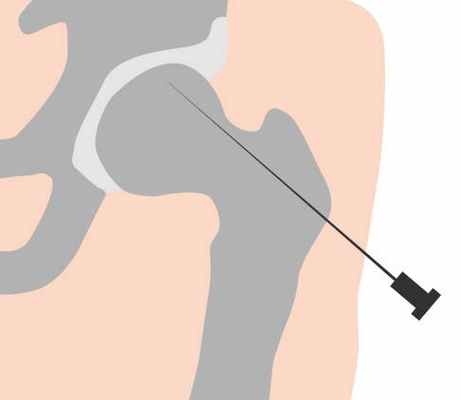

- Биопсия – забор биоматериала для гистологического анализа. По результатам гистологии можно судить о злокачественности процесса и степени его распространенности.

- Операции на бедре с просверливанием отверстий в тазобедренных костях (например, приди-отверстия)